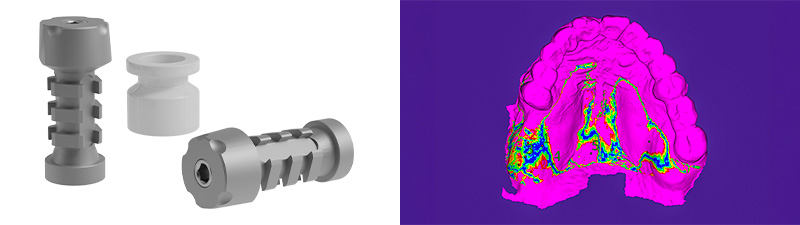

Immédiatement après la suture, des piliers de type « Scan-Transfer » de l’entreprise IPD, ont été placés sur les piliers « Multi-unit » (IPD propose des piliers « multi-unit » pour 25 marques d’implants dentaires et 80 plateformes différentes). Ceux-ci permettent une numérisation précise à l’aide d’un scanner intra-oral, selon un protocole spécifique qui évite toute distorsion de l’empreinte dans les zones édentées.

Fig. 04 : Scan-Transfer de l’entreprise IPD, matching des empreintes réalisé dans le logiciel Exocad.

Dans des cas plus complexes, des repères temporaires additionnels peuvent être ajoutés pour faciliter le matching. Les Scan-Transfers présentent la particularité que le matching s’effectue uniquement sur la partie supérieure de la tête du pilier d’empreinte numérique. La partie inférieure, quant à elle, peut recevoir des éléments destinés à combler les espaces édentés, ce qui facilite le scannage et réduit les risques de distorsion. La vis de fixation du Scan-Transfer, une fois vissée, est exactement au même niveau que le pilier prothétique, elle affleure la tête du pilier de numérisation. C’est un indicateur que le pilier est correctement positionné et qu’aucune déviation n’a eu lieu en raison de la présence d’un obstacle anatomique.